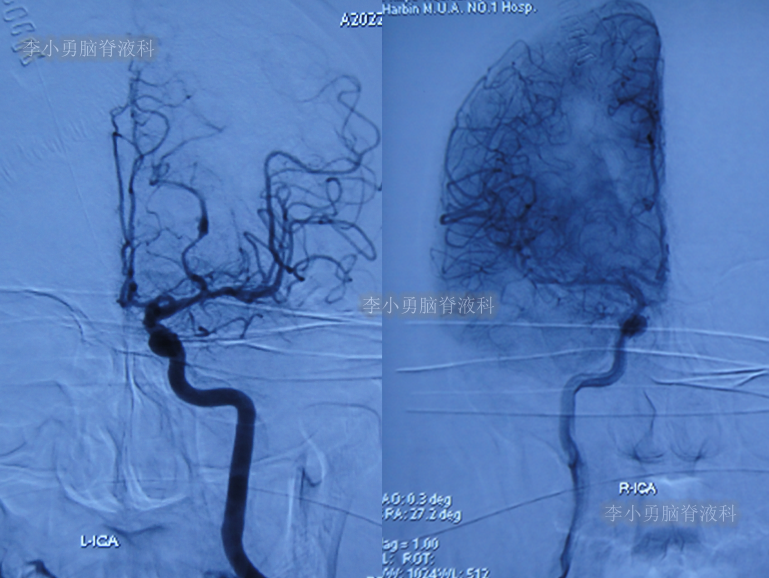

当天查头颅头DSA(图-2)示大脑后交通动脉瘤。

图-2:2022年3月17日头颅DSA

2022年3月18日(脑出血后3天),给予了脑动脉瘤栓塞术治疗。